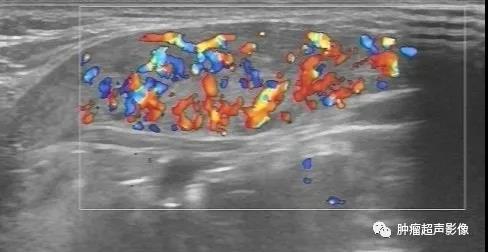

异位甲状腺(迷走甲状腺):正常甲状腺位置未见甲状腺回声,颌下见甲状腺样组织回声,回声不均,血流丰富,类似甲亢表现(推测功能不足,代偿性)